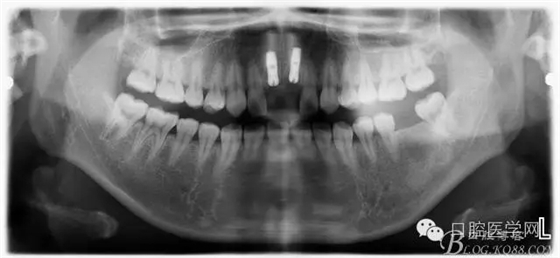

設(shè)計(jì)方案:11.21種植(選用登騰系統(tǒng),GBR植骨)12.22 RCT后樁冠修復(fù),牙齦瓷修復(fù)。

一期手術(shù)后3-6個(gè)月可做二次修復(fù),接愈合基臺(tái),拆線后10-15天根據(jù)情況可以采模型做牙冠。